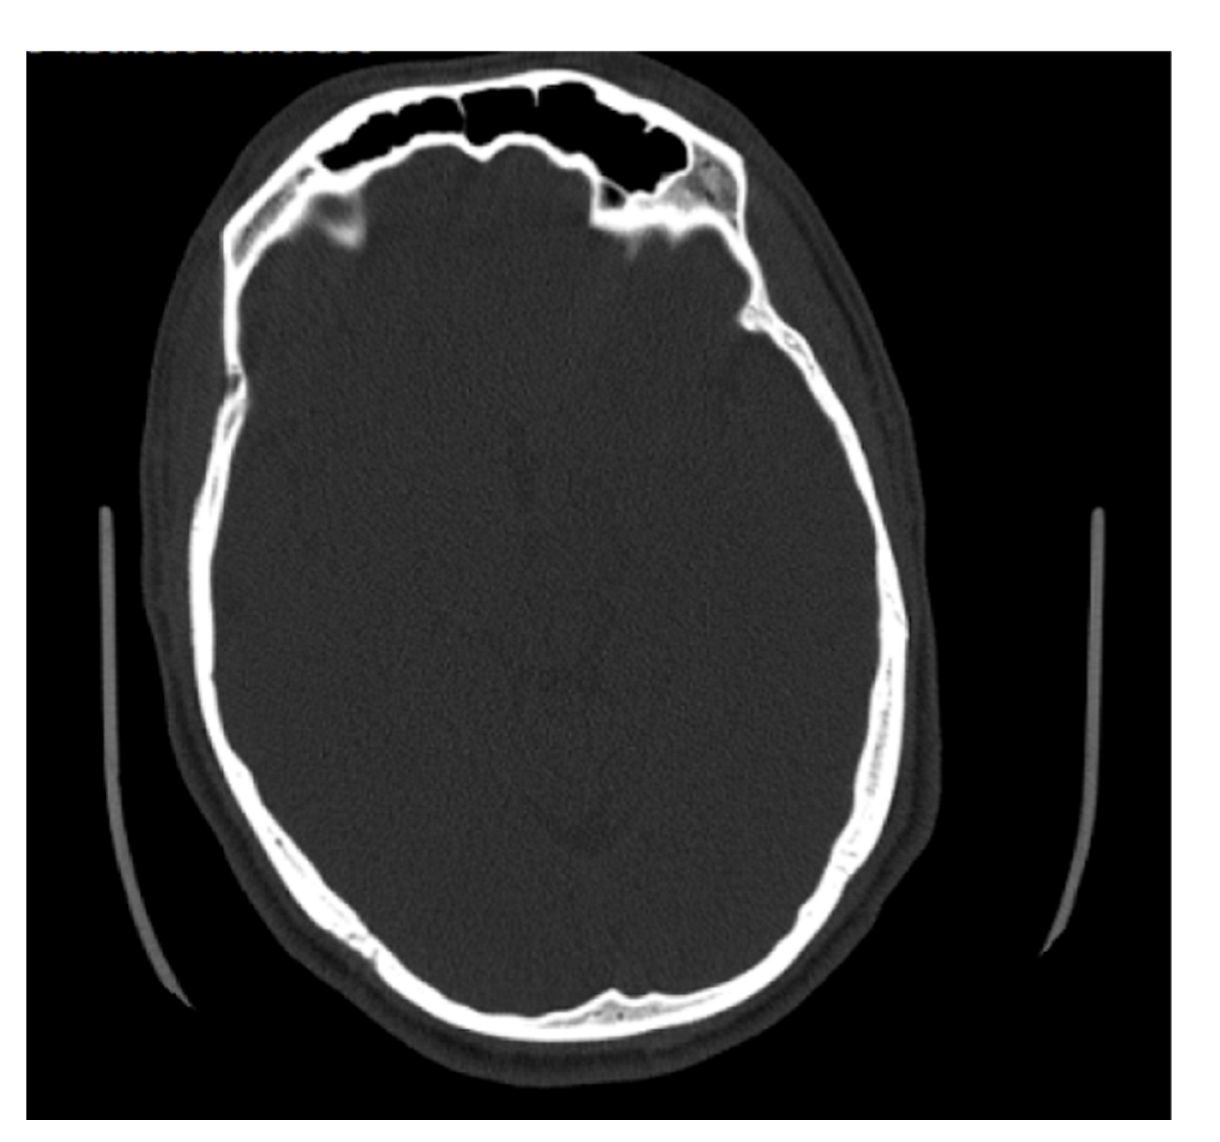

Some of the files received from BMC included slices on the axial plane in addition to the coronal and sagittal orientations (Figure 7). The methods used to determine maximum depth in this study were completed on the sagittal slices; however, the axial slices were significantly better suited for efficiently determining the maximal depth, and in future studies, the axial plane is recommended to measure maximum depth. The axial plane limits any discrepancies in determining where the frontal sinus connects with the nasal cavity and ethmoid sinus, and instead presents a clearer representation of the most anterior and posterior portions of the frontal bone. This orientation also allows for both left and right portions of the frontal sinus to be viewed simultaneously, allowing for an easier estimation of maximum depth. Simple procedures and standardized methods are critical to this kind of analysis. On radiographs, the analyst does not have to estimate the posterior border of the frontal sinus or demarcate where the frontal sinus transforms into other anatomical structures. While this skill is not difficult to develop, it is a skill that needs to be practiced. The axial orientation would eliminate this concern when taking a maximum depth of the frontal sinus, but the concern is still present when deciding which coronal slices to use for tracing.

Figure 7.

Example of an axial CT image slice useful for measuring frontal sinus depths.